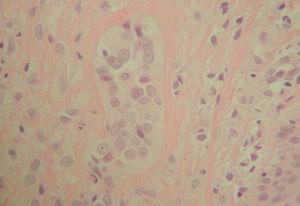

Un paciente varón de 36 años, de origen rumano, sin antecedentes de interés, acudió a consultas de dermatología por la presencia de una lesión en planta de pie izquierdo. Refería que a los 17 años comenzó con una hiperqueratosis, de crecimiento lentamente progresivo y que le molestaba al caminar. Hace 4 años se le realizó una pequeña extirpación en su país de origen, pero el paciente no aportaba informes. Hace 3 años reapareció nuevamente una lesión, que fue creciendo lentamente, y era dolorosa al andar, motivo por el que consultaba. En la exploración física presentaba una placa hiperqueratósica en la región plantar del primer metatarso, no ulcerada, de límites mal definidos y de aproximadamente 2 x 2 cm (fig. 1). Con el diagnóstico clínico de carcinoma verrucoso, se realizó biopsia en la que se observaba una epidermis hiperqueratósica y sin alteraciones aparentes, mientras que en la dermis y grasa se ponía de manifiesto una proliferación tumoral formada por nidos de células endoteliales de aspecto epitelioide redondeadas y poligonales. El citoplasma era eosinófilo y contenía luces intracitoplasmáticas, algunas de las cuales estaban llenas de hematíes. En ciertas áreas, las células se disponían formando canales vasculares. No se observaban figuras de mitosis ni de atipia nuclear (fig. 2). La inmunohistoquímica fue positiva para CD34 y factor VIII (fig. 3) y negativa para S-100 y panqueratinas (fig. 4). Con estos datos se realizó el diagnóstico de HEE.

Fig. 1.--En la región plantar del primer metatarso se observa una placa hiperqueratósica mal definida, de aproximadamente 2 x 1,8 cm, no infiltrada ni ulcerada.

Fig. 2.--En la dermis se observa una masa tumoral compuesta por células eosinófilas, de aspecto poligonal y fusiforme. En algunas de estas células se observa un citoplasma vacuolado.